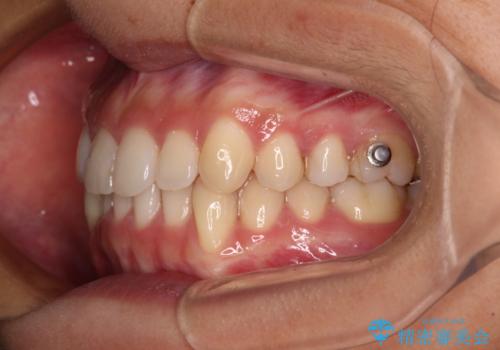

- 下顎の八重歯を気にして来院された患者様です。

マウスピース矯正でもワイヤー矯正でも対応可能であり、マウスピースによる治療を希望されたため、インビザラインを用いることとしました。

下顎前歯にデコボコが集中していたため、顎間ゴムによる後方移動とIPR(歯と歯の間を削ること)により歯列を整えることとしました。

しっかりとマウスピースを装着してくださったおかげで、スムーズに治療を終えることができました。

矯正治療途中で右下奥歯の虫歯治療を近医で行ったようで、既に神経が失活していたと合わせて矯正治療後に補綴治療を行う予定です。